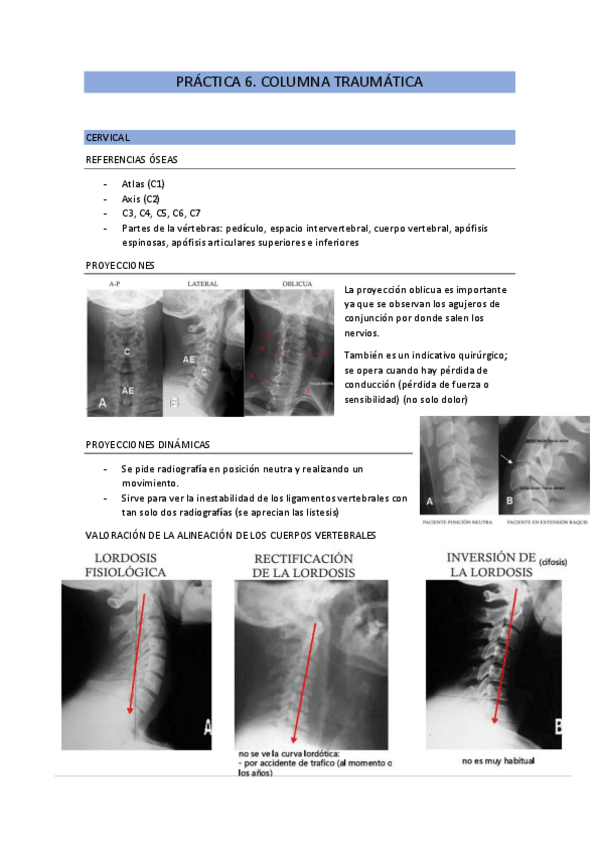

He publicado nuevos practicas de 2º Patología y Enfoque Terapéutico del Aparato Locomotor: practica-6.-columna-traumatica.pdf